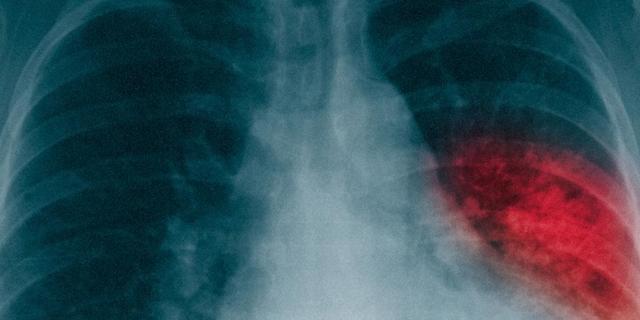

Die Symptome einer Lungenentzündung können oft schwer von einer normalen Erkältung unterscheiden werden. Typische Anzeichen sind Schüttelfrost, Husten, rascher Anstieg der Körpertemperatur, beeinträchtigte Atmung sowie Müdigkeit und kraftlosigkeit. Bei Verdacht auf eine Lungenentzündung sollte ein Arzt konsultiert werden. Die Diagnose erfolgt in der Regel durch Abhorchen und Abklopfen des Brustkorbs sowie verschiedene Untersuchungen wie Blutgasanalyse, Röntgenaufnahmen der Lunge, Ultraschall oder Computertomographie.

Um eine Lungenentzündung zu diagnostizieren, stehen verschiedene Verfahren zur Verfügung. Eine Blutgasanalyse kann Aufschluss über die Funktionsfähigkeit der Lunge geben. Röntgenaufnahmen ermöglichen es Ärzten, Veränderungen in der Lunge festzustellen. Mit Hilfe einer Ultraschalluntersuchung können Flüssigkeitsansammlungen im Brustkorb erkannt werden. Eine Computertomographie liefert detaillierte Informationen über die Lage und Ausbreitung der Entzündung. Bei Verdacht auf eine Infektion können Proben aus der Lunge und den Atemwegen entnommen werden.

Die Symptome einer Lungenentzündung sind oft schwer von denen einer normalen Erkältung zu unterscheiden. Um eine genaue Diagnose zu stellen, führt der Arzt verschiedene Untersuchungen durch, wie das Abhören der Lunge und Röntgenaufnahmen. Diese diagnostischen Maßnahmen helfen dabei, eine korrekte Behandlung einzuleiten und mögliche Komplikationen frühzeitig zu erkennen.

– Blutgasanalyse: Eine Blutuntersuchung, bei der der Gehalt von Kohlendioxid und Sauerstoff im Blut gemessen wird. Dadurch kann die Funktionsfähigkeit der Lunge beurteilt werden.

– Röntgenaufnahmen: Diese dienen dazu, Veränderungen in der Lunge festzustellen und ihre Lage und Größe zu bestimmen.

– Ultraschall: Mit einer Ultraschalluntersuchung kann zum Beispiel ein Pleuraerguss (übermäßige Flüssigkeitsbildung im Brustkorb) festgestellt werden.

– Computertomographie (CT): Eine computergestützte Röntgenuntersuchung, die detaillierte Querschnittsbilder des Körpers liefert und zur genauen Einschätzung der Entzündung in der Lunge verwendet werden kann.

– Gewinnung von Proben aus der Lunge und den Atemwegen: Bei Verdacht auf eine Infektion können Proben des Auswurfs Hinweise auf Keime liefern. Eine Lungenspiegelung mit Spülung der Lungenbläschen kann weitere Informationen über die Ursache und die geeignete Therapie liefern.